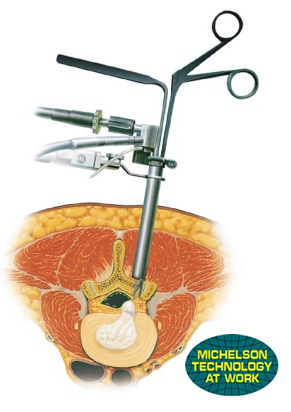

椎間板ヘルニアでは椎間板の中の髄核と呼ばれる部分が神経を圧迫し、腰痛や下肢の疼痛、痺れ、筋力低下などの症状を引き起こします。MEDは内視鏡を使用し、症状の原因となっている髄核を取り出す手術で、従来の方法より切開が小さく16mmの切開となっておりますので、痛みが少なく早期の退院・社会復帰が可能となっております。当院の入院期間は1泊2日となっております。

腰部脊柱管狭窄症や腰椎すべり症により神経が圧迫される原因となる部分を切除し、骨を移植して背骨を固定する手術です。

当院では低侵襲の手術方法を採用し創が26mmと小さい切開で実施しております。

従来の大きく切開する手術方法よりも術後の痛みは少なく、入院期間は4泊5日と早期の退院・社会復帰が可能です。